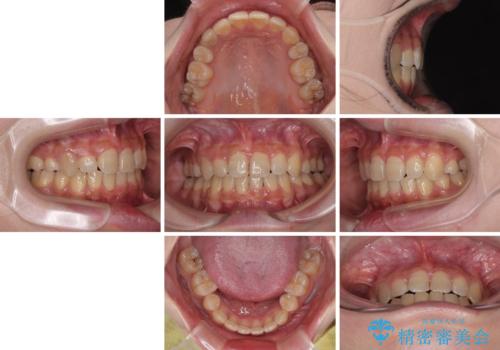

気になる八重歯 ワイヤー装置での抜歯矯正

- 上下の八重歯を気にして来院された患者様です。

非抜歯矯正で歯列を整えると、治療後に口元が今よりも突出する可能性が高かったため、上下左右の小臼歯4本を抜歯し、ワイヤー装置にて矯正治療を行うこととしました。

右上の八重歯の影響で、右側は上顎歯列が前方位の咬み合わせとなってしまっていたため、上顎は第一小臼歯を、下顎は第二小臼歯を抜歯することで咬み合わせや上下正中を調整することとしました。

第二小臼歯抜歯の治療となったため、やや時間はかかりましたが、概ね予想通りの期間で治療を終えることができました。